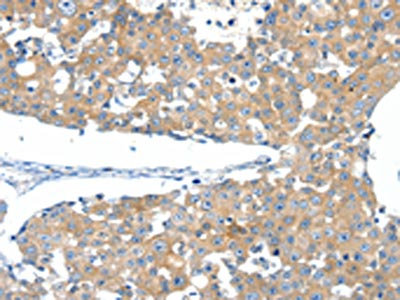

The image on the left is immunohistochemistry of paraffin-embedded Human breast cancer tissue using CSB-PA130335(SSTR3 Antibody) at dilution 1/40, on the right is treated with synthetic peptide. (Original magnification: ×200)

The image on the left is immunohistochemistry of paraffin-embedded Human ovarian cancer tissue using CSB-PA130335(SSTR3 Antibody) at dilution 1/40, on the right is treated with synthetic peptide. (Original magnification: ×200)